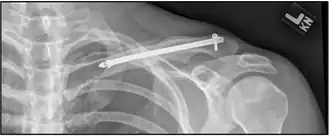

| X-ray of a left clavicle fracture | |

A discontinuity in the bone shape often results from a clavicular fracture, visible through the skin, if not treated with surgery. Surgical procedures often call for open reduction internal [plate] fixation where an anatomically shaped titanium or steel plate is affixed along the superior aspect of the bone by several screws. In some cases, the plate is removed after healing due to discomfort, to avoid tissue aggravation, osteolysis or subacromial impingement. This is especially important with a special type of fixation plate called hook plate.[17] With anatomical plates plate removal is considered an elective procedure that is rarely necessary. An alternative to plate fixation is elastic TEN intramedullary nailing. These devices are implanted within the clavicle's canal to support the bone from the inside. Typical surgical complications are infection, loss of sensation distal the incision due to inadvertent injury of one or several supraclavicular nerves (most common when using a horizontal surgical incision)[18], and nonunion of the bone (failure of the bone to properly fuse together). Major nerve injury to the brachial plexus or vascular injury is extremely rare.[19]